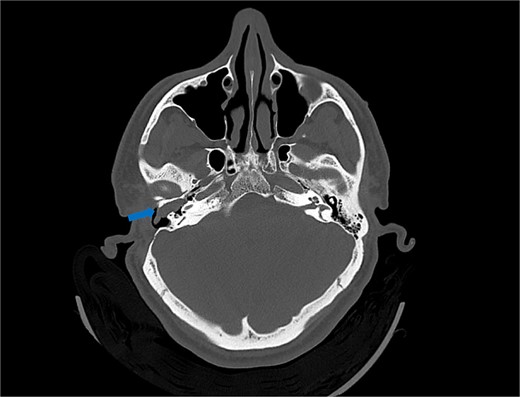

A CT scan of the temporal bones revealed a lesion suggestive of recurrent cholesteatoma (Fig. 1). However, evaluation with preoperative MRI demonstrated a hypervascular lesion in the middle ear extending into the EAC and involving the right epitympanum, making recurrent cholesteatoma less likely (Fig. 2).

Axial view of computed tomography (CT) scan showing a polypoid soft tissue lesion in the floor of the external auditory canal, extending into the middle ear cavity, with erosion of the bony scutum (arrow).